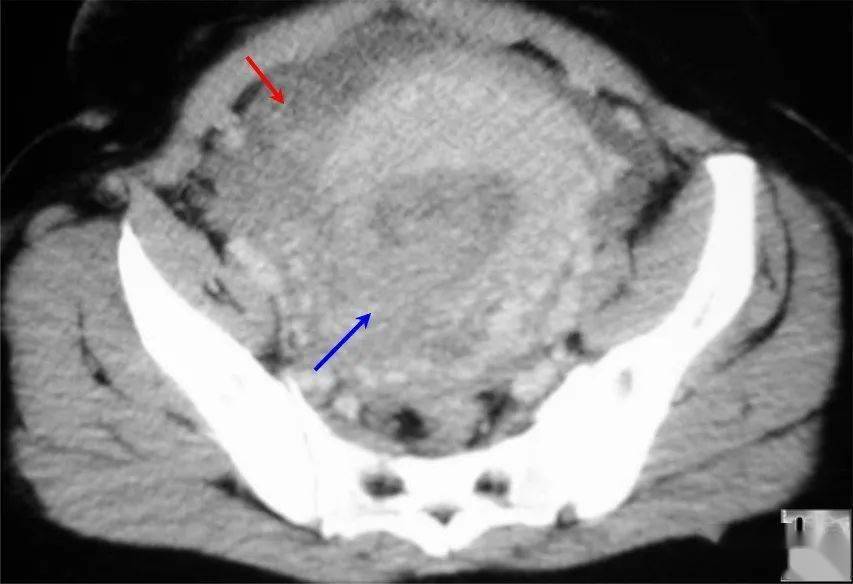

盆腔ct影像,女性盆腔CT影像

盆腔内大量积血(红色箭头.